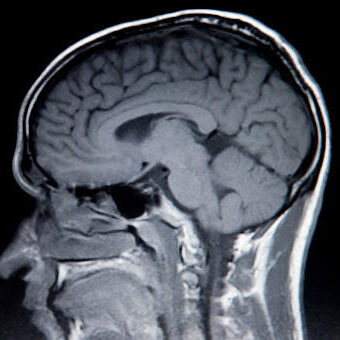

When Chronic Traumatic Encephalopathy (CTE) takes hold, it alters lives in ways that are unimaginable. At Gordon McKernan Injury Attorneys, we understand the profound impact CTE has on families, and we’re here to fight for your future. We don’t just handle cases; we fight for your justice and the compensation you need to rebuild.

Unlike visible personal injuries, brain trauma often remains hidden, making diagnosis difficult. Neurodegenerative brain injuries like CTE require specialized care, and that’s where we come in. At Gordon McKernan Injury Attorneys, we’re dedicated to uncovering these hidden dangers and ensuring victims receive compensation for both present and future challenges.